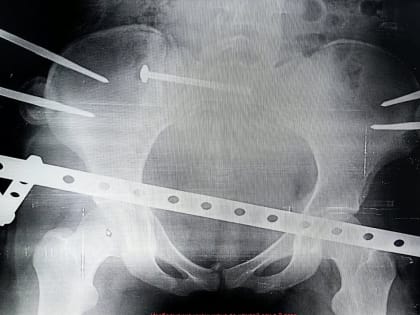

Сургутские травматологи провели уникальную операцию восстановления костей таза без разрезов

Проявить все свое мастерство хирургов заставила семнадцатилетняя девушка-пассажир, которую после ДТП экстренно доставили в клинику.